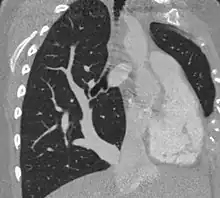

| Scimitar syndrome chest CT | |

Scimitar syndrome, or congenital pulmonary venolobar syndrome, is a rare congenital heart defect characterized by anomalous venous return from the right lung (to the systemic venous drainage, rather than directly to the left atrium).[1] This anomalous pulmonary venous return can be either partial (PAPVR) or total (TAPVR). The syndrome associated with PAPVR is more commonly known as Scimitar syndrome after the curvilinear pattern created on a chest radiograph by the pulmonary veins that drain to the inferior vena cava.[2] This radiographic density often has the shape of a scimitar, a type of curved sword.[2] The syndrome was first described by Catherine Neill in 1960.[3]

The anomalous venous return forms a curved shadow on chest x-ray such that it resembles a scimitar. This is called the Scimitar Sign. Associated abnormalities include right lung hypoplasia with associated dextroposition of the heart, pulmonary artery hypoplasia and pulmonary sequestration. Incidence is around 1 per 100,000 births.[4]

The diagnosis is made by transthoracic or transesophageal echocardiography and selective pulmonary angiography.[5] More recently by CT angiography or MR Angiography.